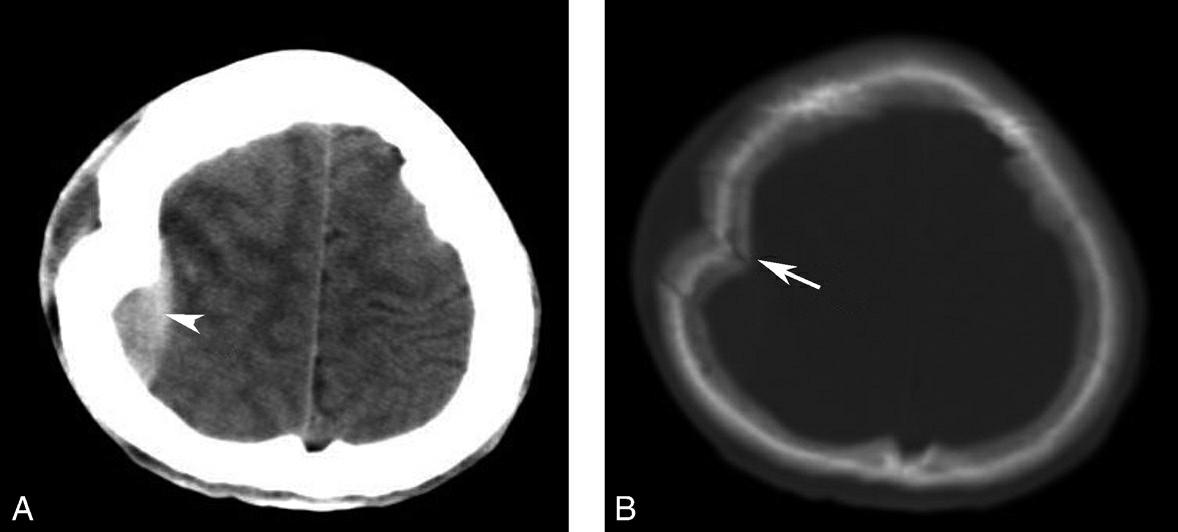

图1-2-3 鼻咽癌颅底骨质破坏

A.横断面;B.横断面(骨窗)

骨窗示左侧岩尖、斜坡、左侧蝶骨大翼骨质破坏、受侵(白箭),肿瘤经破裂孔侵入颅内(黑箭头)